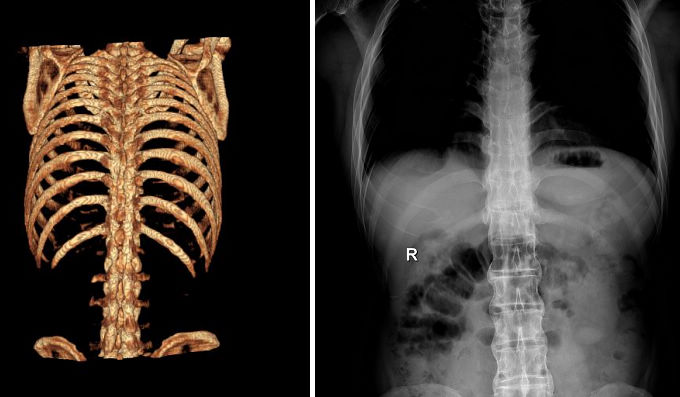

AS ①晚期 ②重度 病史:5年+

治疗后骶髂关节疼痛消失,腰椎前屈、背伸侧弯活动自如,膝关节无压痛感,复查血沉、C反应蛋白、等各项检查均已达到临床康复的标准。